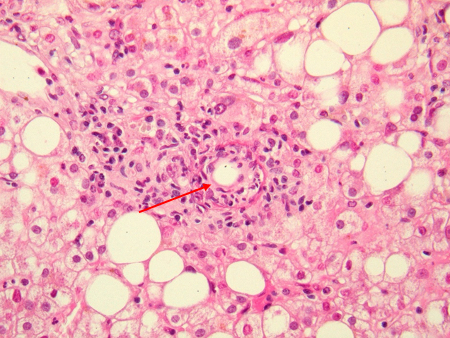

Granuloma em forma de "donut" no fígado, característico da hepatite por Coxiella burnetii. Observe a morfologia específica do granuloma em forma de "donut". Não se observa a presença de bactérias neste granuloma

Hubert Lepidi, Institut Hospitalo-Universitaire Méditerranée Infection